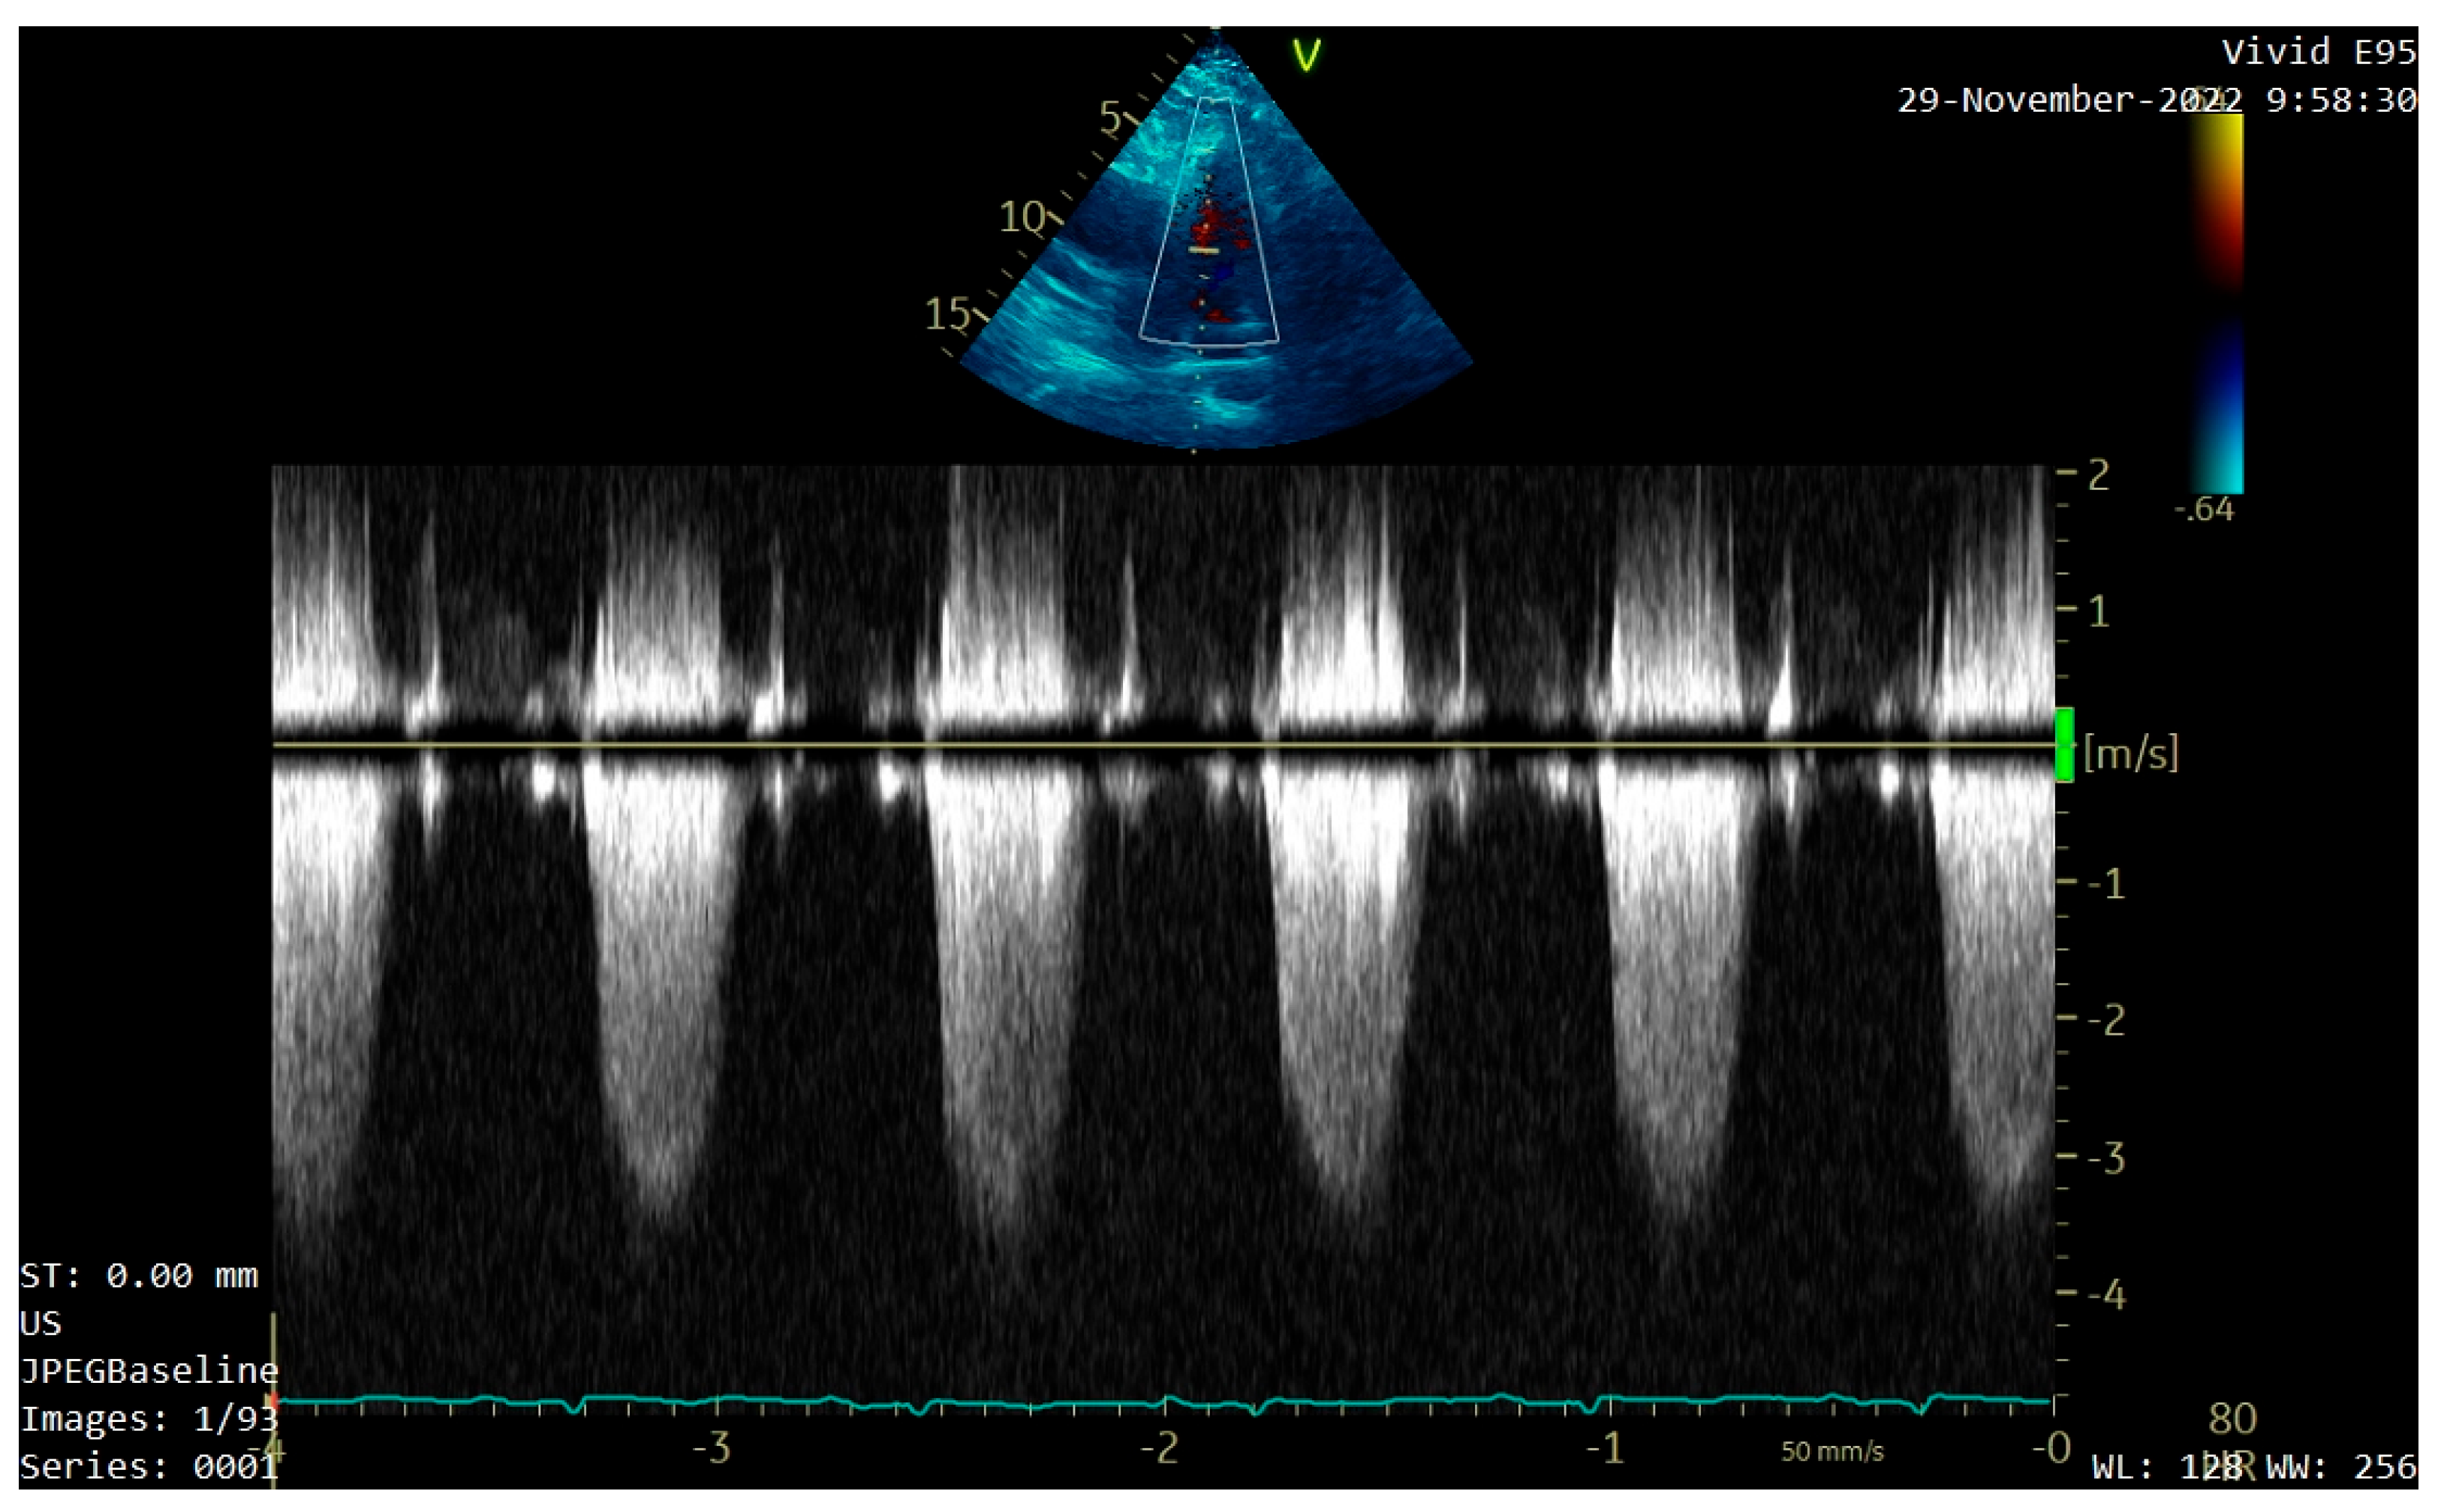

A transthoracic echocardiography (TTE) was performed. It showed a round 25/30 mm, 6.5 cm2 intracardiac mass attached to the right ventricle outflow tract (RVOT) wall by a 5 mm thick pedunculus (Figure 1a), which prolabated through the pulmonary valve in systole, thus causing severe obstruction at this level with a maximum gradient of 70 mmHg (Figure 1b and Figure 2). The pulmonary valve itself presented no structural abnormalities, but the right ventricle was dilated (50 mm at the base) with a slightly decreased systolic function (TAPSE = 15 mm), a moderate tricuspid regurgitation and paradoxical interventricular septum motion being also observed due to right ventricular pressure overload. The left ventricle was not dilated and had a preserved systolic function, and only a mild mitral regurgitation was noted.

Figure 1. Transthoracic echocardiography (TTE) showing: (a) a round intracardiac mass attached to the right ventricle outflow tract (RVOT) wall by a pedunculus (white arrow); (b) turbulent flow on Color Doppler caused by the tumor’s severe obstruction of the RVOT (white arrow).

Figure 2. TTE Continuous Wave Doppler showing severe RVOT obstruction.